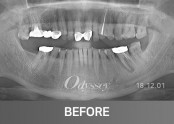

임플란트 181210

임플란트 181229

임플란트 181105

임플란트 181208